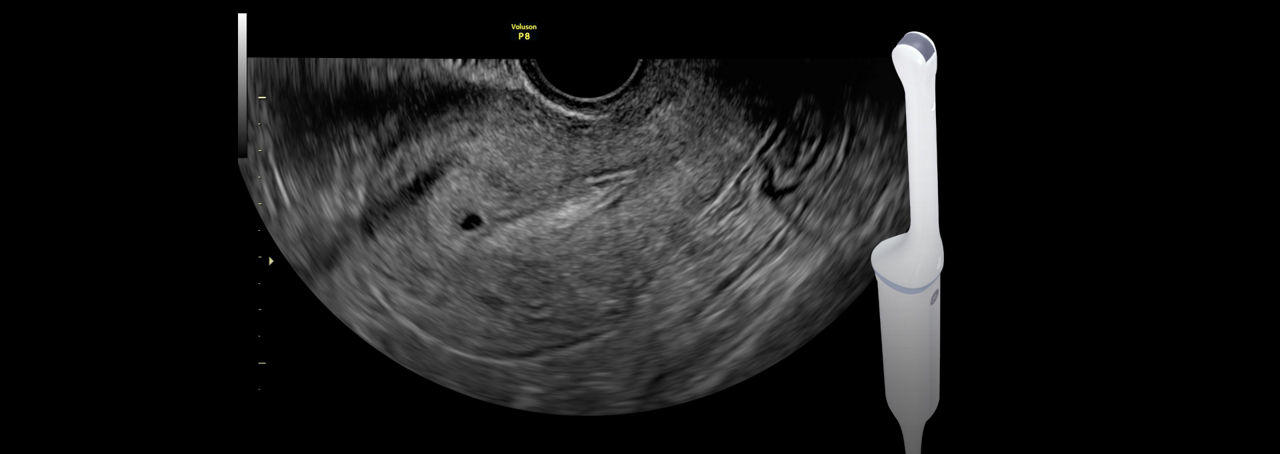

Imaging Simplified

Simply place the probe to get the information you need. Built on Voluson Core Architecture, the P8 delivers excellent imaging across all types of patients and exams.